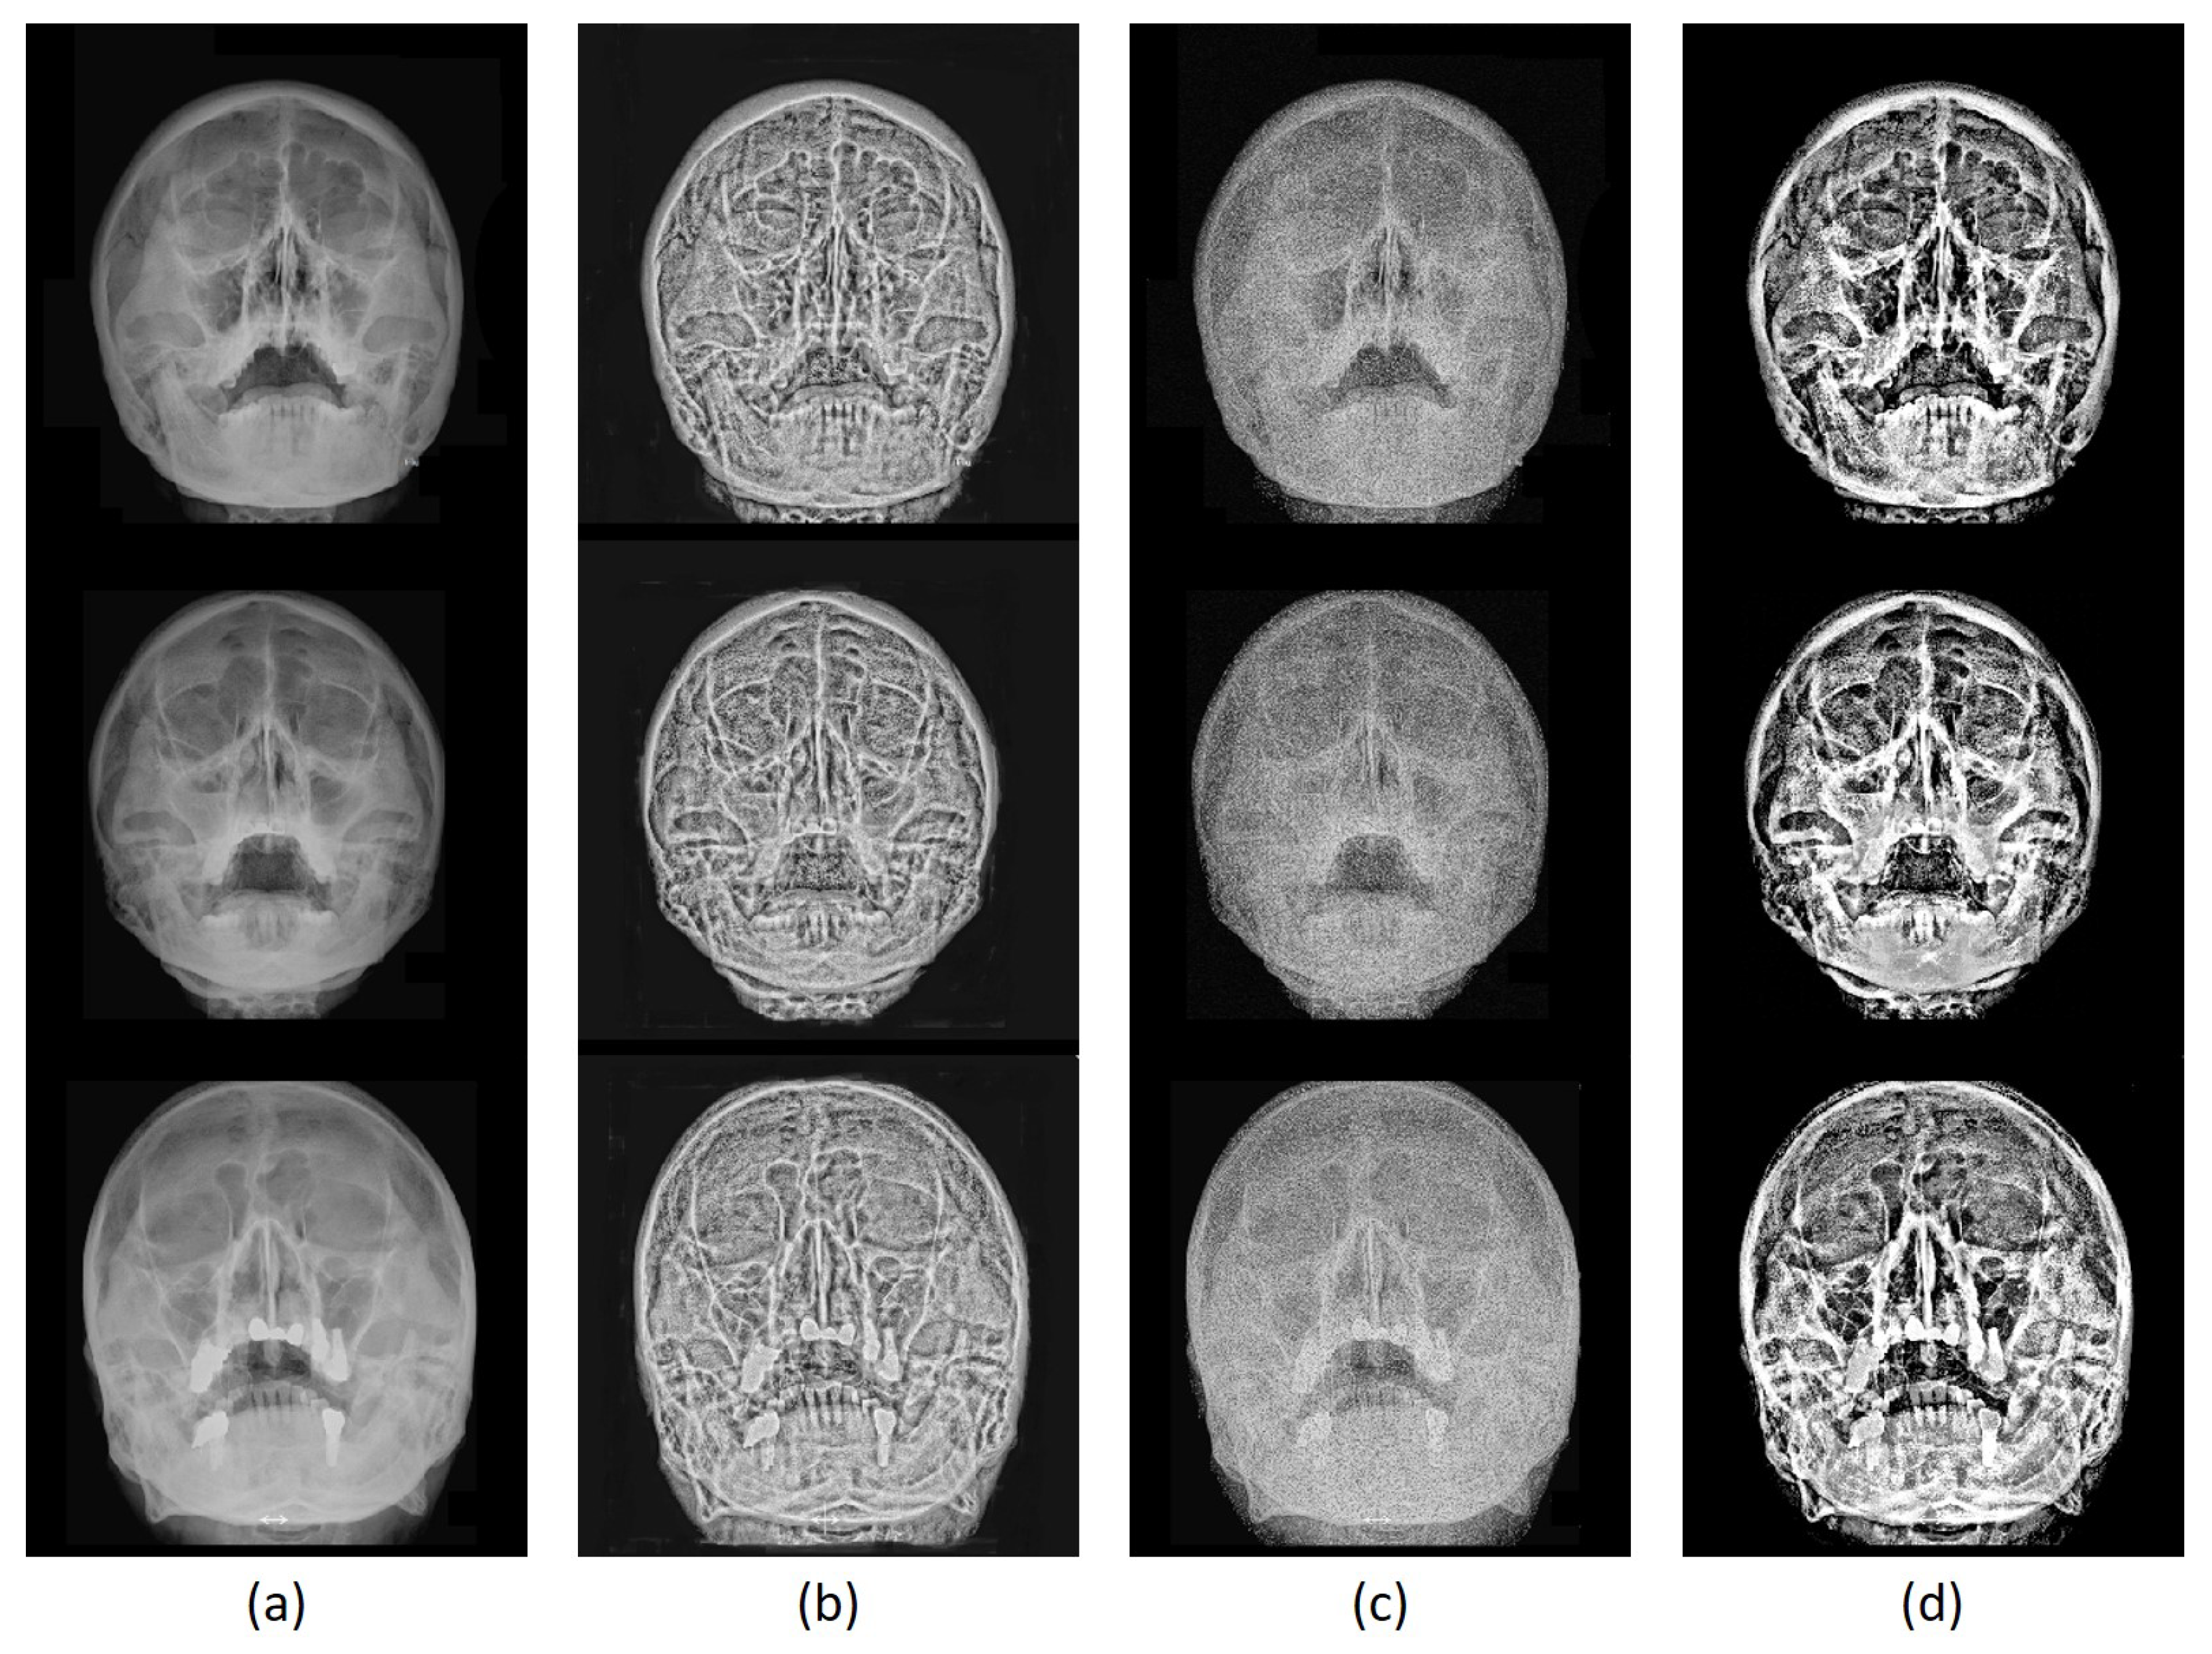

3.3. Image Enhancement Evaluation

3.3.2. Qualitative Evaluation